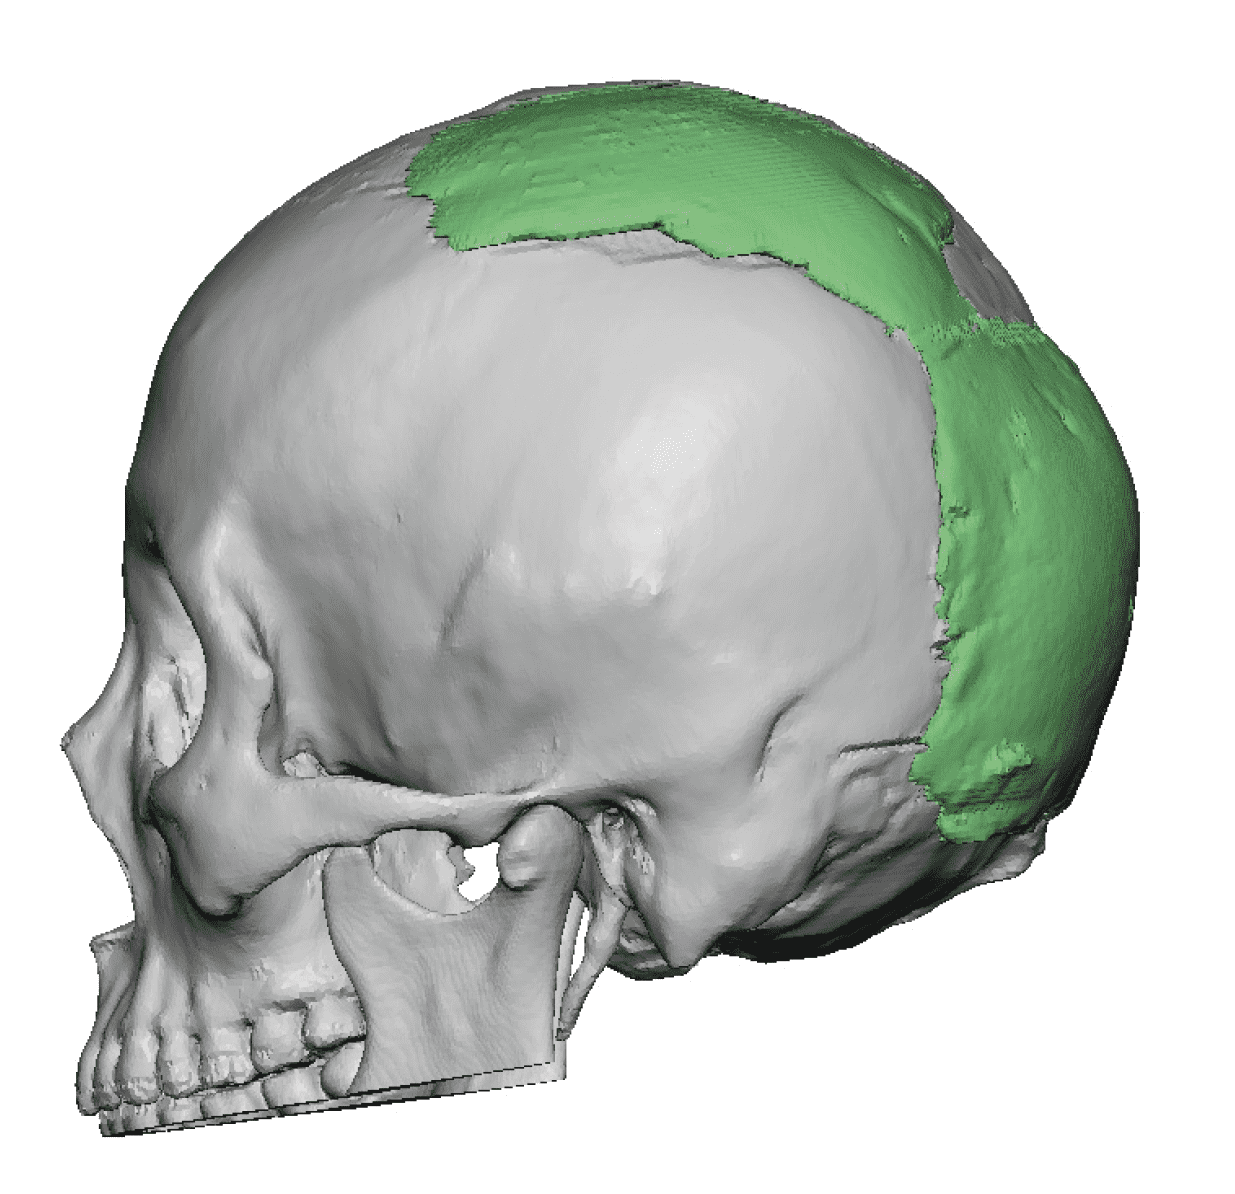

Patient 110

Desire for head shape asymmetry improvement as the final stage of total skull reshaping surgeries. (previous skull implants are in green color)

Placement of custom temporal implant through an incision behind the ear.

Desire for head shape asymmetry improvement as the final stage of total skull reshaping surgeries. (previous skull implants are in green color)

Placement of custom temporal implant through an incision behind the ear.